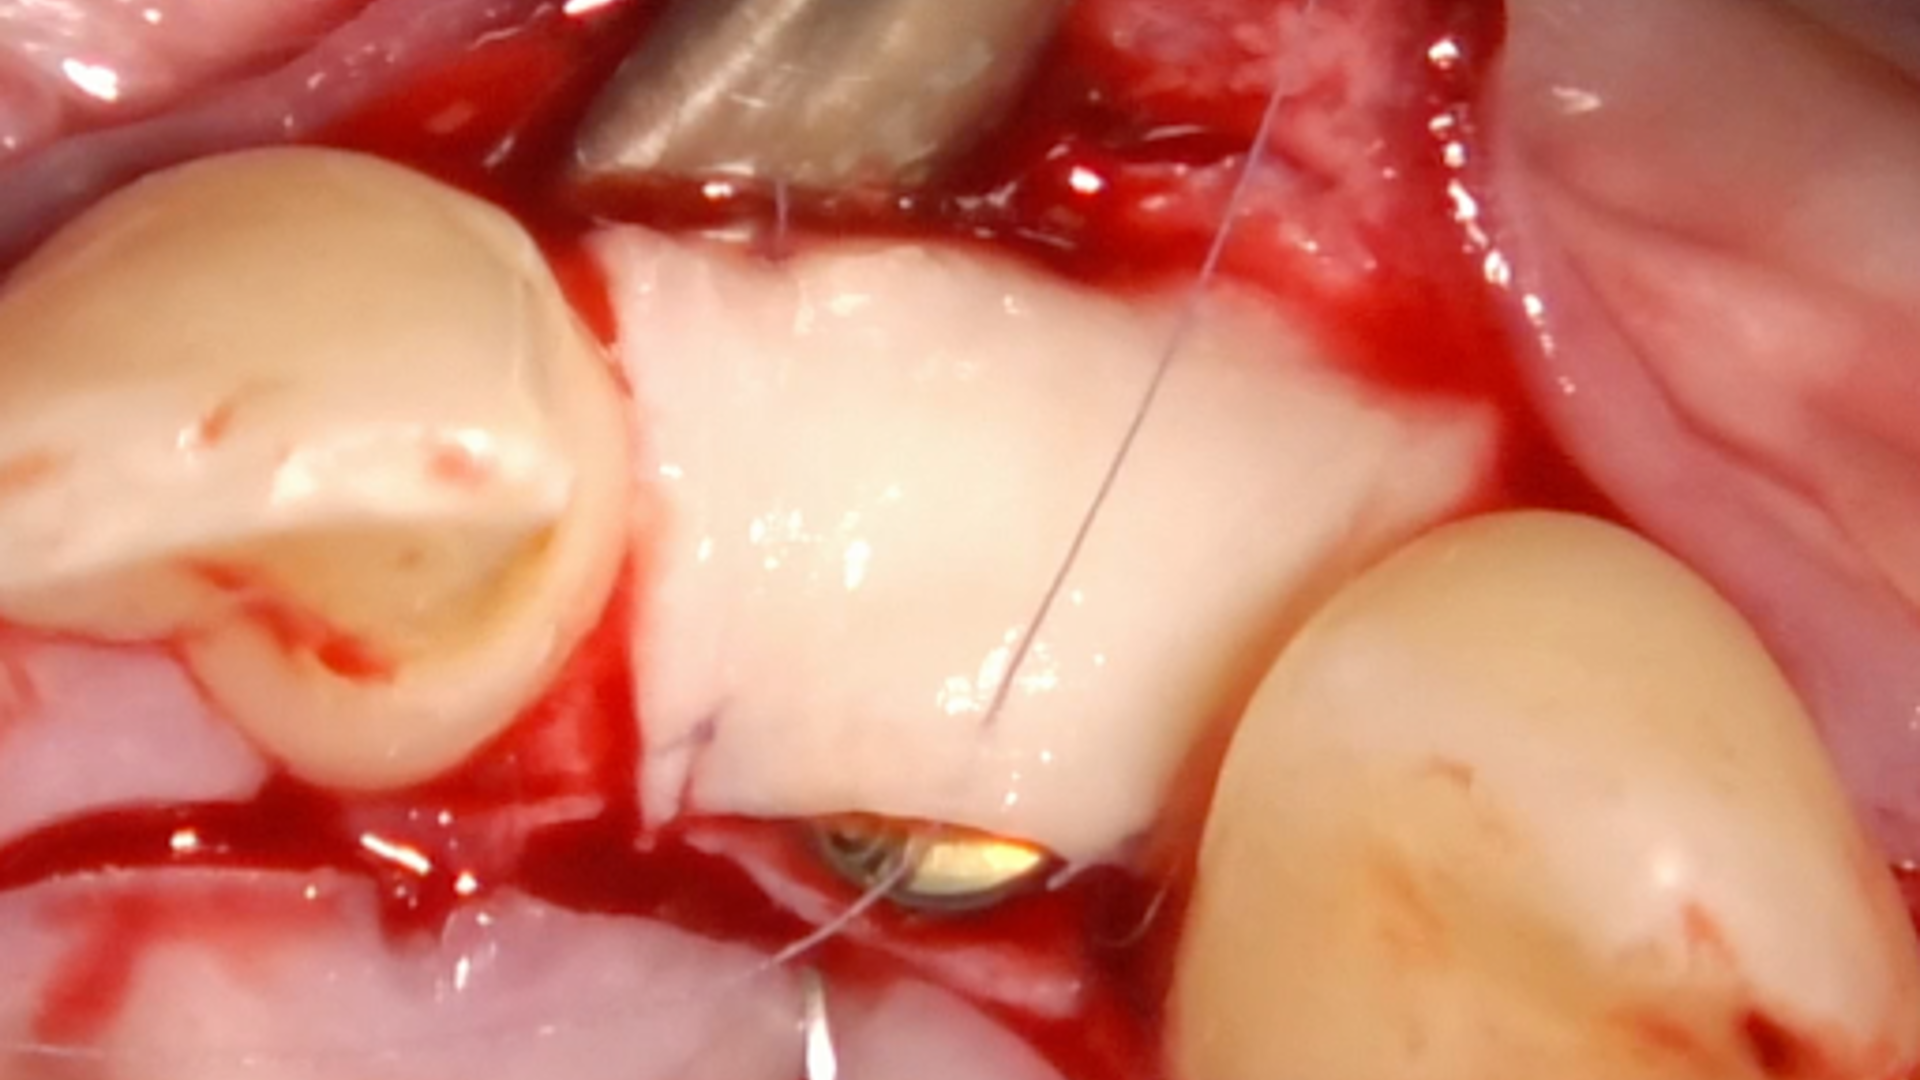

2nd ReLIVE Surgery - Soft tissue augmentation for a guided implant placement at the level of lateral incisor

Hands-On Video Part 3 - Connective tissue graft harvesting and disepithelisation

Hands-On Video Part 4 - Suture protocol